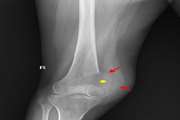

Treatment of a calcaneal unicameral bone cyst by percutaneous CT guided cement injection using a double needle technique: A case report 1403/12/01 - 11:11